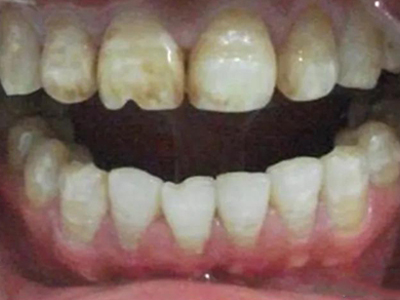

牙釉质发育不全牙齿变薄图

牙釉质发育不全患者的牙齿有色泽和透明度改变,表面出现白垩色釉质,同时牙齿顶端变透明、变薄,但患者可能无敏感、疼痛等自觉症状。